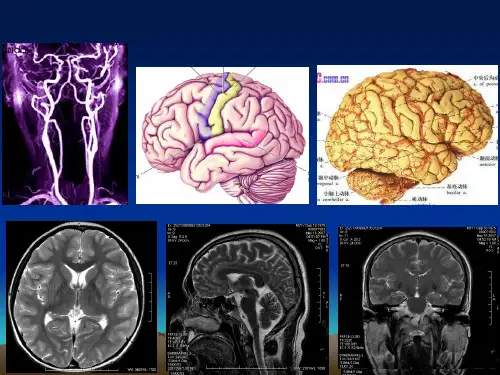

脑血管断层解剖

磁共振血管造影

(magnetic resonance angiography,MRA)

一、脑血管的特点

脑血管病的发病和死亡率居首位。 脑重量仅为体重的2%,但其耗氧量 则占全身耗氧量的20%,其所需血供 占心输出量的15%。脑组织本身不能 储存能量,更不能进行糖的无氧酵解, 故其对氧的需求特别高。尽管存在脑 底动脉环,但这种调节有一定的限度。

缺血缺氧4分钟即可造成神经元的死亡。 脑各类神经元对缺氧敏感性由高至低依次为:

脑动脉壁很薄,类似颅外同等大小的静脉

大脑的动脉分为: 皮质支cortex branches(营养皮质和浅层髓质) 中央支central branches(供应基底核、内囊及间脑), 二者均自成体系,互不吻合